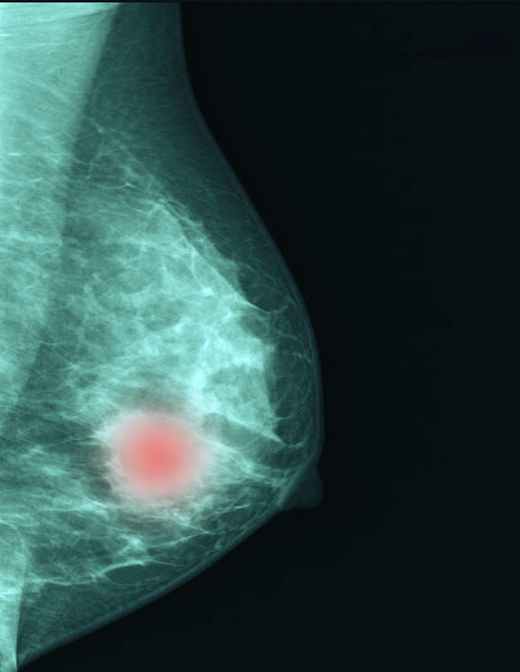

유방암 초기에는 증상이 없어 검진을 통해 우연히 진단되는 경우가 많다. 가장 흔한 증상은 유방에서 덩어리가 만져지는 경우다. 대개 통증이 없고 단단하며 경계가 불규칙한 덩어리다. 이외에도 유두에서 피가 섞인 분비물이 나오거나, 유두에 습진이 생겨 잘 낫지 않는다면 유방암을 의심해볼 수 있다. 유방 피부가 움푹 패거나 유두가 움푹 들어간 경우, 겨드랑이 부위 림프샘이 만져지는 경우, 유방 전체 피부가 빨갛게 부어오르며 통증이 있거나 열감까지 같이 나타나는 경우에도 유방암을 의심할 수 있다.

운동이 유방암의 가장 좋은 예방법이다. 지속해서 운동하면 에스트로겐이 적게 생성되고 복부에 지방이 덜 쌓일 뿐만 아니라 인슐린 수치도 낮춘다. 하루 30분씩 일주일에 3~4일 걷기, 자전거 타기, 수영, 에어로빅, 등산 등 유산소 운동이 도움 된다.

에스트로겐의 효과를 떨어뜨리는 식습관도 중요하다. 동물성 지방이나 오메가-6 지방 대신 오메가-3 지방을 섭취하는 게 좋다. 황록색 채소, 과일, 콩, 곡물 등 섬유질이 많은 식품 섭취를 늘린다. 당을 과도하게 섭취하지 않는 것도 중요하다. 당 흡수가 늘수록 당을 산화시키기 위해 인슐린이 더 많이 분비돼서다. 인슐린이 많이 분비되면 에스트로겐 수용체와 상호작용이 활발해져 유방암 발병 위험을 높일 수 있다.

혹시 모를 가능성에 대비해 유방암 정기 검진을 1~2년 간격으로 꾸준히 받는 게 중요하다. 초기 유방암은 치료 성적이 매우 좋기 때문에 암이 생겼더라도 조기에 발견하는 게 매우 중요하다.